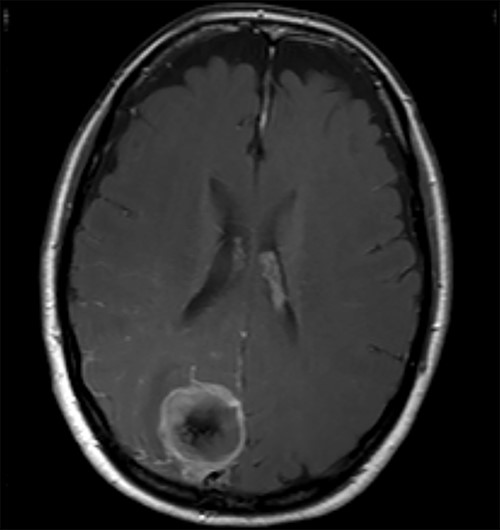

The operation was successful with a post-operative MRI within 48 h demonstrating complete resection of the tumour and resolution of the cystic lesions, but persisting intraparenchymal oedema (Fig. 3). The patient had an uncomplicated two-day stay in a neurosurgery high dependency unit postoperatively before being stepped down to the general neurosurgery ward. She was reviewed by the microbiology team and worked up for the source of infection. Blood cultures, urine cultures, CXR and transthoracic echocardiography were all negative for a source of infection. Intra-operative pus cultures isolated MSSA. The histopathology of the tumour was Meningioma WHO Grade 1 with large areas of necrosis and secondary abscess formation. She was discharged feeling well 5 days later after a satisfactory biochemical and clinical response. She was given a weaning course of steroids and a 6-week course of intravenous ceftriaxone via a PICC line as an outpatient as per microbiology advice. Ophthalmology assessment 3 months after discharge confirmed a left inferior quadrantonopia and preserved visual acuity. Repeat MRI and clinic review 8 weeks later showed no radiological residual tumour or oedema (Fig. 4), and the patient’s limb function recovered completely but had ongoing visual symptoms.

T1 weighted axial MRI postgadolinium enhancement within 48 h post-operatively. Small amount of enhancement within the surgical bed remains. Good resection margins with vasogenic oedema. This may represent a small residual. The rim-enhancing cystic lesions appear to have resolved.